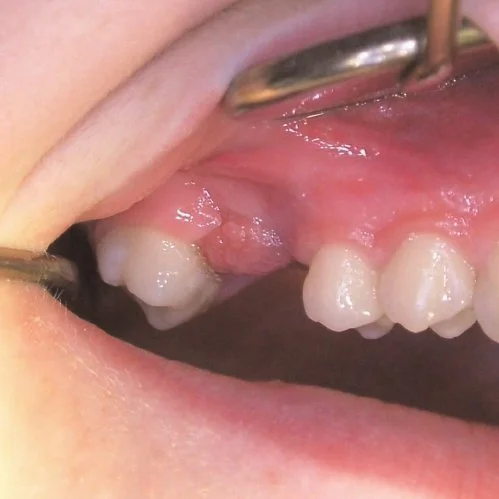

Гранулема - это локальное воспаление в тканях пародонта, ограниченное плотной соединительной тканью. Патологическому росту грануляционной ткани или эпулису способствует инфицирование при пародонтите, после экстракции зуба или стоматологического лечения корневых каналов.

Хронический гранулематозный процесс часто не имеет симптомов. Лишь изредка допустимы боли при надкусывании, дискомфорт на прием кислой или холодной пищи. При снижении иммунитета или развития осложнений, симптомы гранулемы будут следующими:

• Локальный отек и гиперемия в зоне воспаления;

• Появление гноя между тканями десны и коронкой, иногда сопровождающегося клиническими признаками периостита или флюса.